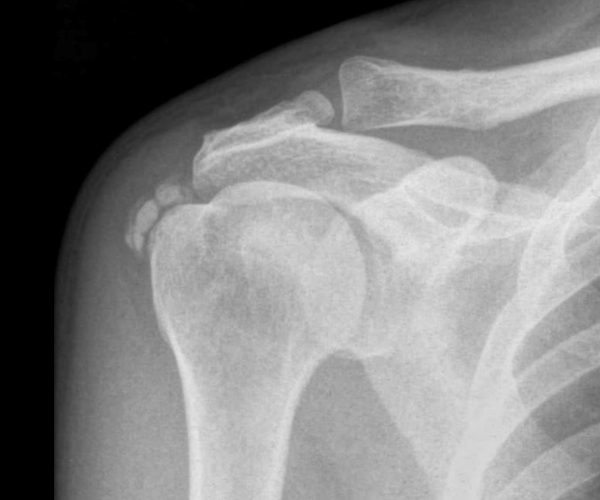

어깨 관절은 우리몸에서 운동 범위가 매우 크고, 다른 관절들에 비해서 매우 복잡한 구조를 가지고 있습니다.

어깨통증을 유발하는 질환도 다양하기 때문에 적합한 치료가 필요합니다.

어깨 관절 와순은 상완골이 어깨뼈에서 이탈하지 않도록 어깨 관절 주변의 날개뼈를 둘러싸고 있는 섬유연골조직을 말합니다.

이 연골판이 찢어져 관절에서 떨어져 나오면서 통증을 유발합니다. 어깨 탈구(빠짐) 시 거의 대부분 관절 와순 파열이 동반되어 적절한 치료를 받지 않는 경우 재발의 가능성이 있습니다.

팔을 올리거나 젖힐 때 통증이 나타나고, 주로 어깨 뒤쪽에 통증이 나타나며 뚝 하는 소리가 납니다. 스포츠, 레져를 즐기는 활동성이 강한 분들에게 발생하는 경우가 많습니다.